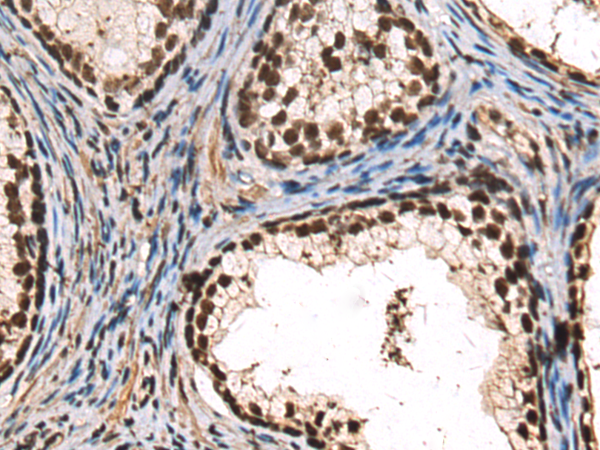

分类: 科研抗体货号: P10598别名: RCH2; SRP1; IPOA5; NPI-1应用: IHC反应种属: Human, Mouse, Rat